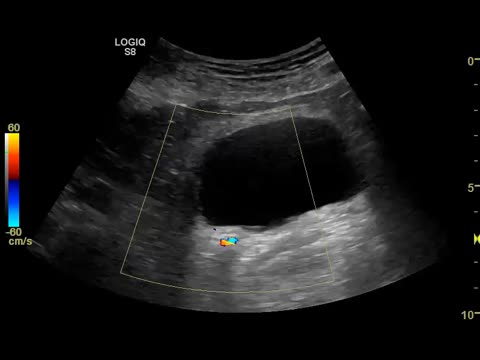

Ecográficamente las litiasis se observan como estructuras hiperecogénicas puntiformes o con forma de teja, con 2 artefactos ecográficos que apoyan el diagnóstico, la sombra acústica posterior y el artefacto centelleo con Doppler color (fig. 2 y video 3).

Se localizan en cualquiera de los cálices renales, en la pelvis renal, uréteres y vejiga. Son visibles con ecografía cuando son superiores a unos 4mm y son más fáciles de visualizar cuando se localizan en los calices o en la vejiga; y mucho más difíciles en el trayecto de los uréteres13.

Cuando una litiasis se desplaza hacia el uréter produce clínica compatible con un cólico renoureteral (dolor lumbar, náuseas, vómitos, …), y ecográficamente se observan signos de uropatía obstructiva, es decir, hidronefrosis o dilatación de la pelvis renal y/o los calices renales. Es en estos casos en los que hay que intentar determinar la localización de la litiasis que está produciendo la obstrucción. Con ecografía se localiza con facilidad si se encuentra en la pelvis renal o en el uréter distal, y es más difícil en el uréter medio por la interposición de meteorismo intestinal.